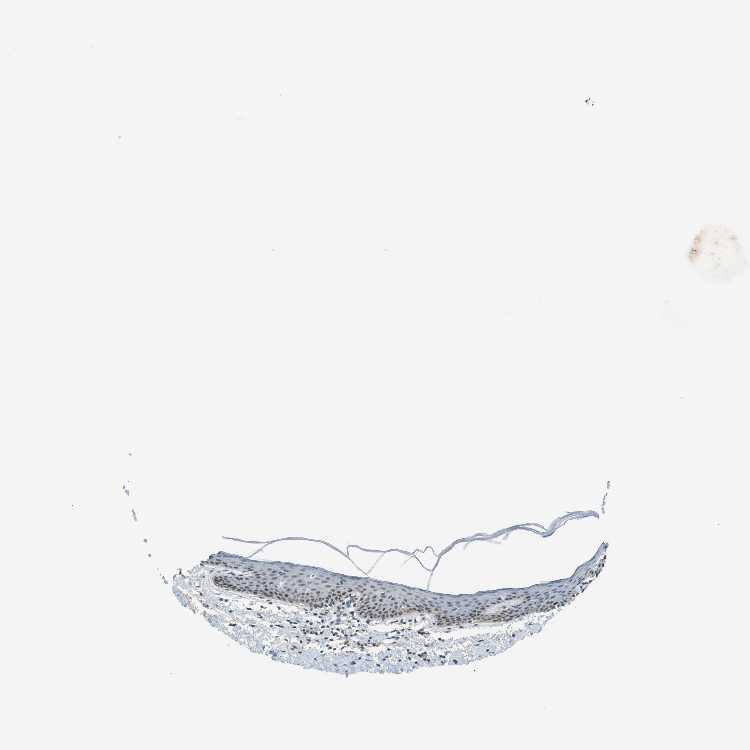

SKIN 1 - Antibody stainingi

Antibody staining in the annotated cell types in the current human tissue is reported as not detected, low, medium, or high, based on conventional immunohistochemistry profiling in selected tissues. This score is based on the combination of the staining intensity and fraction of stained cells.

Each image is clickable and will lead to virtual microscopy that enables deeper exploration of all samples and also displays staining intensity scores, fraction scores and subcellular localization as well as patient and tissue information for each sample.

Antibody CAB017548

Cells in basal layer Low

Cells in corneal layer Not detected

Cells in granular layer Not detected

Cells in spinous layer Low

Endothelial cells Low

Extracellular matrix Not detected

Fibrohistiocytic cells Low

Langerhans cells Low

Lymphocytes Low

Melanocytes Not detected

Vascular mural cells Not detected